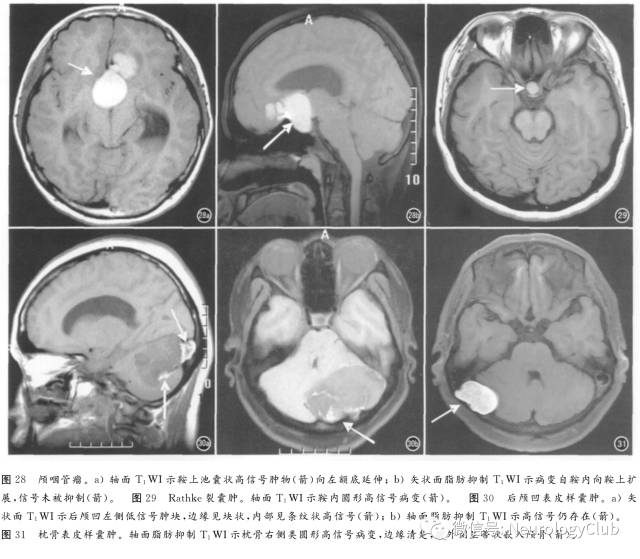

1. 颅咽管瘤

多有囊变,囊性部分可呈短T1信号甚至很高信号(图28),为蛋白质与胆固醇成分所致,少数由于钙化和出血。鉴别诊断包括垂体瘤卒中与累及鞍区的星形细胞瘤。CT检查显示钙化(80%)有助于本病诊断。

3. Rathke裂囊肿

来自Rathke裂上皮残余,其50%位于鞍内,25%位于鞍上,25%跨越鞍上及鞍内。内含不同含量的蛋白质、粘多糖、细胞碎屑、胆固醇,因此T1WI与T2WI信号可为低、等及高信号(图29),增强扫描一般无强化。鉴别诊断包括垂体瘤出血及颅咽管瘤。

4. 表皮样囊肿

仅含表皮组织,包括去鳞状化细胞与角化碎屑,最常见于桥前区与CPA池、鞍上及鞍旁、后颅凹及颅骨内(图30、31),典型表现为各序列信号与脑脊液信号近似,但FLAIR序列上为不均匀高信号,DWI显示扩散受限,少数呈短T1信号,似皮样囊肿,内含较高胆固醇成分。高信号表皮样囊肿需与脂肪瘤及皮样囊肿鉴别,不同之处是无化学位移伪影及脂肪抑制无信号下降。